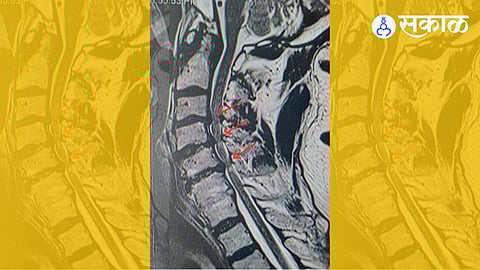

अनेकांना स्पाँडिलोसिस हा एक आजार आहे, असं वाटतं. खरं तर स्पाँडिलोसिसची प्रक्रिया ही शरीराचं वय वाढताना मणक्यामध्ये होत जाणारे बदल असतात. केस पांढरे होण्यासारखी ही प्रक्रिया आहे. .मात्र, ही प्रक्रिया अतिरिक्त प्रमाणात घडली किंवा त्यामुळे मणक्याच्या कॅनॉलमध्ये असलेल्या मज्जारज्जूवर किंवा बाहेर पडणाऱ्या नसांवर दाब आला, तर स्थिती गंभीर होऊन आजाराची स्थिती निर्माण होते. त्यातच भर म्हणजे प्रत्येक व्यक्तीच्या मणक्याची रचना जेनेटिकली वेगळी असते, त्यामुळे स्पाँडिलोसिसच्या प्रक्रियेचा परिणाम वेगवेगळा होऊ शकतो.वयोमानापरत्वे प्रत्येकाला हा त्रास कमी-अधिक प्रमाणात होत असतो. आपल्या दोन मणक्यांमध्ये ‘डिस्क’ (गादी/कुर्चा) असते. ही ‘शाॅक ॲब्सॉर्बर’ व ‘बॉल बेरिंग’चं कार्य करत असते. डिस्कचा मधला भाग जेलीप्रमाणे मऊ असतो. त्यात पाण्याचं प्रमाण अधिक असतं. झीज सुरू होते, तेव्हा हे पाण्याचं प्रमाण आटायला लागतं..डिस्कची उंची कमी होत जाते व दोन मणके एकमेकांच्या जवळ यायला लागतात. त्यामुळे शरीराला जाणीव होते, की या भागात काही तरी गडबड आहे. आपल्या शरीराचा गुणधर्म असा आहे, की कुठंही अस्थिरता जाणवली, की तिथं जास्त हालचाल न होण्याचे उपाय योजले जातात. त्यामुळे प्रथम मानेच्या भागातले स्नायू आकुंचन पावतात व कडक होतात. त्यामुळे मान ‘अवघडते.’त्यानंतर हळूहळू या ‘अस्थिरतेवर’ उपाय म्हणून ‘डिस्क’च्या अवतीभवती नवीन कॅल्शियम साचायला लागतं व हळूहळू त्याचं नवीन हाडात रूपांतर होतं. हे हाड वरून व खालून ‘चोची’प्रमाणे वाढतं. ‘अस्थिर’ भाग सांधण्याच्या शरीराच्या प्रयत्नांचा हा भाग असतो. अशा प्रकारांची हाडांची टोकं मणक्यातल्या मागच्या भागातल्या सांध्यांमधूनसुद्धा वाढतात..मज्जारज्जूभोवतीच्या इतर काही भागांतल्या सांध्यांमधूनसुद्धा वाढत जातात. मज्जारज्जूभोवती असलेल्या इतर काही लिगामेंटस्मध्येसुद्धा कॅल्शिअम जमा व्हायला लागतं. या प्रक्रियेलाच स्पॉंडिलोसिस म्हणतात. मणक्यांची झीज वयाच्या २५ वर्षानंतर सुरू होते व ५० वर्षानंतर ९५ टक्के लोकांच्या एक्स-रेमध्ये कमी-अधिक प्रमाणात स्पॉंडिलोसिस असतो.अधूनमधून मान अवघडणं, मणके एकमेकांना सांधले गेल्यानं मानेची हालचाल नेहमीप्रमाणे न होणं, मान कडक होणं अशी लक्षणं बहुतांश लोकांमध्ये वयानुसार दिसतात. अनेक लोकांमध्ये यापुढे प्रकरण जात नाही. मात्र, स्पॉंडिलोसिसची प्रक्रिया नेहमीपेक्षा खूप जास्त झाल्यास मज्जारज्जू व नसांवर दाब येऊ शकतो. तसंच काही लोकांमध्ये मणक्यातील कॅनॉल (ज्यातून मज्जारज्जू व नसा जातात) जन्मत:च चिंचोळा असतो, त्यातच या वाढलेल्या हाडांचा दाब आला, तर ‘दुष्काळात तेरावा महिना’ अशी स्थिती होते..मज्जारज्जूचा दाबचालताना (विशेषत: अंधारात चालताना) तोल न सांभाळता येणं.पायामध्ये जडपणा वाटणं. पायातील शक्ती कमी वाटणं.चालताना पायातील चप्पल निसटणं.तळहातात बधिरपणा येणं. क्लिष्ट कामं करणं अवघड जाणं. (उदा. बोटांनी बटन लावणं, नाडी बांधणं इत्यादी क्रिया करणं अवघड व अशक्य होत जातं.) आजार वाढले, तरी तळहाताची झीज झालेली दिसते. कारण स्नायूंचा आकार आकसायला लागतो. बोटं वाकडी होऊ लागतात.आजार वाढले, तर पायात कडकपणा येतो. पाय गुडघ्यात वाकले जातात. चालणं, हातानं काम करणं अशक्य होतं..आजार आणखी वाढल्यास लघवीवरचा व नंतर संडासवरचा ‘कंट्रोल’ जातो. .नसेवरचा दाबकधीकधी मानेतील मणक्यातून बाहेर पडणाऱ्या नसेवर दाब येतो. यात एका बाजूलाच लक्षणं दिसतात.एका बाजूची मान, खांदा दुखणं.खांद्यापासून कळ अथवा मुंग्या सुरू होऊन दंडात व हातात पसरतात. ही कळ असह्य असते.दंड, हात किंवा तळहातातील स्नायूंची शक्ती कमी होणे. कधी कधी कळा न येतासुद्धा फक्त शक्ती कमी होऊ शकते. याला ‘वेदनारहित’ नसेवरचा दाब म्हणतात. दोन मणक्यांच्या मधून बाहेर पडणारी नस एका गोलाकार बोगद्यातून बाहेर येते. ‘स्पॉंडिलायसिस’चं वाढलेलं हाड या बोगद्यात घुसल्यास नसेवर दाब येतो व हातात कळा, मुंग्या, कमजोरी इत्यादी लक्षणं दिसतात.स्पाँडिलोसिसचं आजारात रूपांतर झाल्यास ते गांभीर्यानं घेणं गरजेचं आहे. मेंदू व मणक्यातल्या पेशी दाबामुळे नष्ट झाल्या, तर परत तयार होत नाहीत. मानेच्या स्पाँडिलोसिसबाबतचे उपाय आणि काही लक्षणांबाबतचे गांभीर्य याबाबत पुढच्या लेखात..सकाळ+ चे सदस्य व्हा ब्रेक घ्या, डोकं चालवा, कोडे सोडवा!शॉपिंगसाठी 'सकाळ प्राईम डील्स'च्या भन्नाट ऑफर्स पाहण्यासाठी क्लिक करा.Read latest Marathi news, Watch Live Streaming on Esakal and Maharashtra News. Breaking news from India, Pune, Mumbai. Get the Politics, Entertainment, Sports, Lifestyle, Jobs, and Education updates, मराठी ताज्या बातम्या, मराठी ब्रेकिंग न्यूज, मराठी ताज्या घडामोडी. And Live taja batmya on Esakal Mobile App. Download the Esakal Marathi news Channel app for Android and IOS.